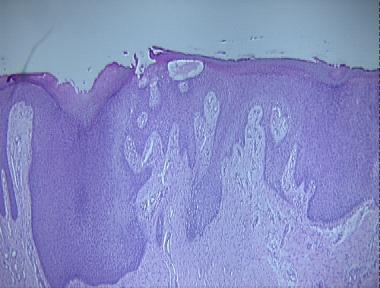

pseudocarcinomatous hyperplasia

Histologic Features